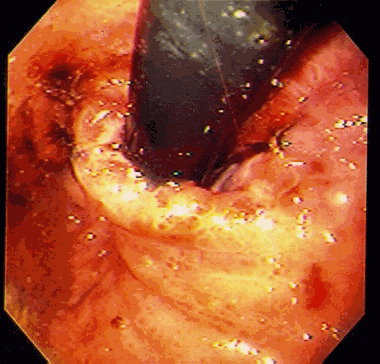

As alterações da gastropatia hipertensiva portal são mais evidentes na mucosa do corpo e fundo do estômago. Os aspectos endoscópicos incluem um padrão de eritema fino, difuso e pontilhado, rash escarlatiniforme ou o padrão conhecido como “pele de cobra” ou “mosaico”, onde se observa áreas avermelhadas, pequenas e poligonais delimitadas por bordas deprimidas e amarelo claras5-8. A gastropatia severa é caracterizada pela presença de pontos vermelho escuros ( “cherry red spots” ) e áreas de hemorragia mucosa difusa ( “gastrite hemorrágica” )5,8. Em estudos endoscópicos com grande amostragem de cirróticos assintomáticos, mais que 50 % apresentam sinais de gastropatia hipertensiva portal, sendo o achado mais comum o padrão mosaico ou em pele de cobra no estômago proximal8,9.

Em 1994, o NIEC (New Italian Endoscopic Club) propôs nova classificação para padronizar as descrições da gastropatia hipertensiva portal10. A classificação se baseia em 4 sinais endoscópicos elementares (tabela 2).

| Classificação da gastropatia hipertensiva portal (Milão –1994) |

| 1. Padrão mosaico ( mosaic-like pattern – MLP ), graduado como leve, moderado ou severo |

| 2. Marcas vermelhas ( red marks – RM ), que incluem lesões puntiformes vermelhas ( red point lesions – RPL ) e pontos vermelho cereja ( cherry red spots – CRS ) |

| 3. Pontos marrom escuros ( black Brown spots – BBS ) |